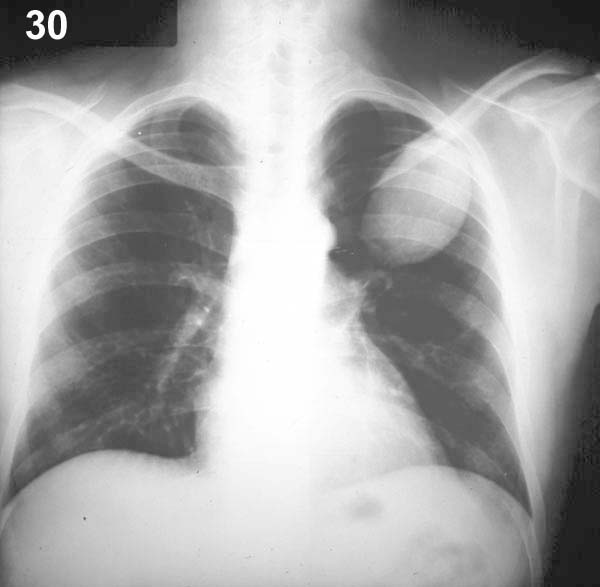

Esquema 30

Comentario placa 30

En la masa del lóbulo superior izquierdo llama la atención lo regular de su forma ovoidea y la nitidez de los bordes. Esto sugiere la posibilidad de un quiste, lo que constituye sólo una hipótesis ya que, generalmente, la radiografía no puede identificar el elemento que define anatómicamente a un quiste, cual es la existencia de una pared propia definida. Si está lleno de líquido o mucus, como es frecuente, la imagen radiográfica es similar a la de un nódulo o de una masa. El diagnóstico seguro puede hacerse recurriendo a TAC o, en casos con contacto parietal, a ecografía. En el caso presente, la imagen se debe a un quiste hidatídico, eventualidad que debe tenerse presente si se plantea estudiar una masa mediante una punción transtorácica por el peligro de shock anafiláctico. Cuando el quiste tiene un contenido aéreo la imagen cae bajo la denominación general de cavidades, que veremos a continuación.